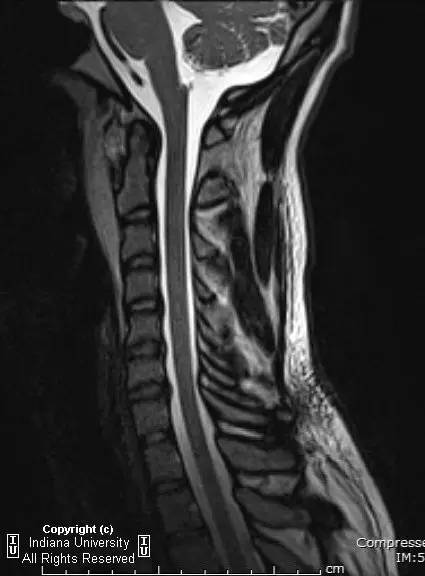

【影像学表现】

CR: C1侧块相对C2侧块外侧移位约5 – 6 mm,符合Jefferson骨折。椎体周围软组织明显肿胀。MR: 椎体周围间隙可见血肿。覆膜完整。寰枕前韧带断裂。寰枢前韧带完整。左侧横韧带从C1侧块的内侧分离,CT对应在C1侧块内侧见小撕脱骨折。翼状韧带完整。寰枕后韧带完整。前纵韧带和后纵韧带完整。黄韧带完整。

Jefferson骨折(Jefferson fracture)是前后弓均累及的C1环粉碎性骨折。Jefferson骨折为头顶受打击并轴向载荷的结果,力从颅骨经枕骨髁传递到颈椎,C1侧块在枕骨髁和C2上关节面之间被压缩,基于侧块的形状产生向心力而导致C1爆裂骨折。齿状突开口位或冠状位重建CT图像应仔细观察双侧C1和C2关节侧块间有无偏移。虽然C1侧块相对C2上关节面侧方移位提示存在骨折,但在X线片上有时难以发现骨折线。MR可显示相应的韧带损伤。

警告:C1异常时单侧或双侧寰枢椎侧方偏移可达2 mm,而Jefferson骨折通常偏移3 mm或以上。